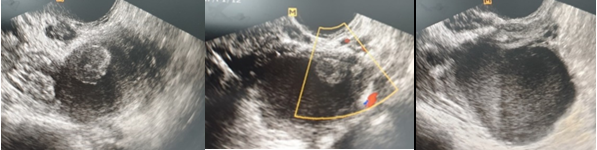

Case 4: A 17-year-old girl came to the hospital with acute lower right abdomen discomfort, nausea, trouble walking, and irregular menstruation. The lower abdomen was not soft on physical examination, and the right adnexa were somewhat painful. An enlarged, hemorrhagic, torted right ovary was seen on ultrasound, with Doppler imaging revealing outer flow with a negative core. Torsion of the right adnexa with teratoma was discovered during a laparotomy. Hemostasis was performed after the teratoma was excised (Figure 4). The diagnosis was confirmed by histology.

Figure 4 Large, hefty cysts and immature cystic teratomas that are benign. With solid component, peripheral cysts (the string of pearls sign) might be visible; the cysts are unilateral in ovarian torsion with aberrant ovary shape.